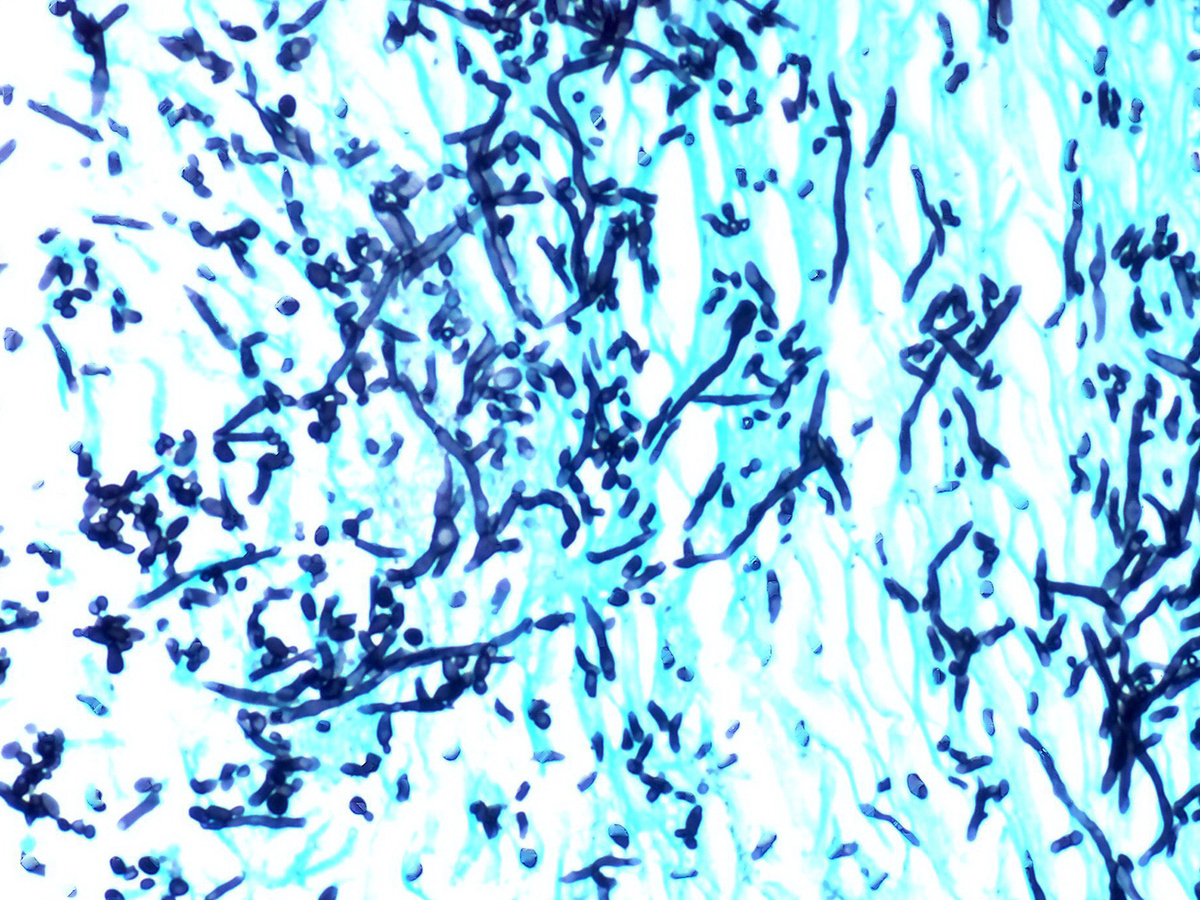

При появлении симптомов грибка стопы рекомендуется обратиться к врачу-дерматологу, который, проведя необходимые исследования, установит диагноз и назначит лечение. Диагноз устанавливается на основании и микроскопическом исследовании кожи стоп или кусочков ногтя, а также на культуральном методе исследования (посев грибка на питательную среду и его дальнейшее изучение).